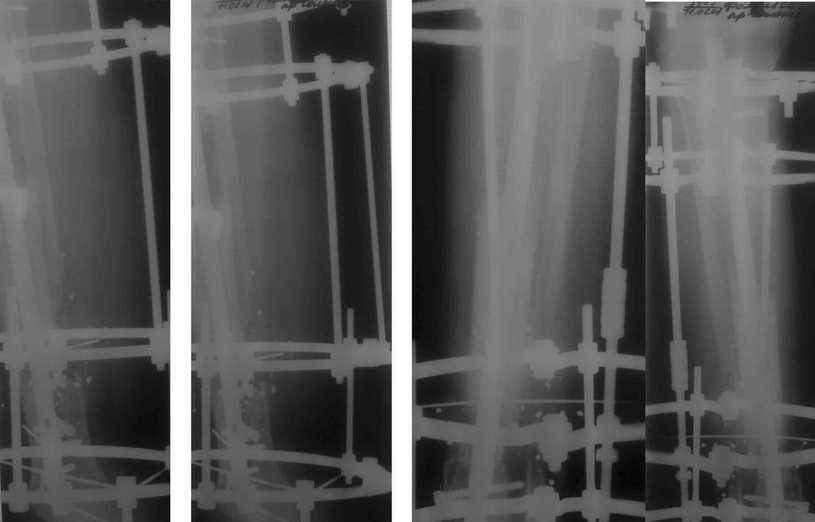

Продолжение обсуждения Больному была выполнена операция. после демонтажа аппарата Илизарова столкнулись с "прямо на глазах" сокращением регенерата. Гвоздь сквозь регенерат удалось провести без технических трудностей. Сложности были с репозицией отломков, что связано с выраженным остеопорозом, их короткими размерами. Пришлось применить полер-винт. Выполнили блокирование. По причине укорочения регенерата пришлось повторно смонтировать аппарат Илизарова и начать транспорт фрагмента на гвозде (14 мм). Больному разрешена ходьба с дозированной нагрузкой на больную ногу. Контрольные рентгенограммы прилагаются. Нынешняя ситуация породила ряд вопросов и замечаний: 1)Как долго удерживать аппарат без риска повторного укорочения регенерата? 2)Когда можно будет разрешить полную нагрузку на больную конечность? 3) Нам видится, что больной уже с момента постуления должен "вестись" по стандартизированному протоколу, чтобы избежать тех трудностей с которыми столкнулись мы в момент операции. Существует ли подобное у вас? 4)Выполнял ли кто-нибудь замещение дефекта кости транспортом фрагмента по Илизарову на гвозде? 5)Считаем необходимым наличие промежуточных отверстий в гвозде для блокирования фрагмента, чтобы воспрепятствовать укорочению регенерата.

Контрольные рентгенограммы прилагаются.

к сожалению малоинформативные из-за качества :(